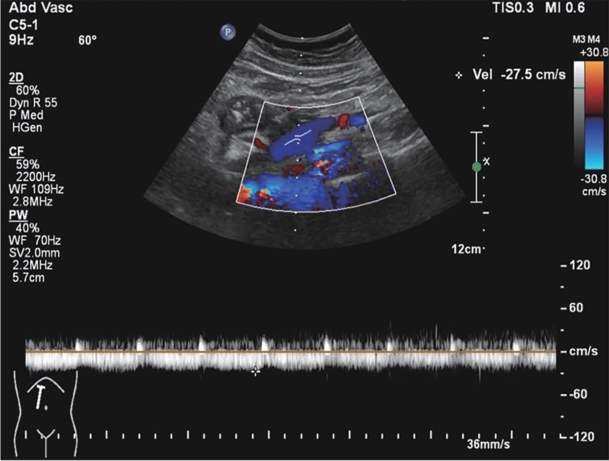

Large spontaneous splenorenal shunt embolization combined with anticoagulant therapy in treatment of portal vein thrombosis: A case report

Ju HUANG, Xiaoze WANG, Xuefeng LUO, Li YANG

2025, 41(8): 1639-1642. DOI: 10.12449/JCH250825

Abstract(504) HTML (172) PDF (3328KB)(67)

Abstract:

Portal vein thrombosis (PVT) is a common and severe complication in patients with liver cirrhosis, and alterations in portal hemodynamics are closely associated with the development of PVT. The presence of large spontaneous splenorenal shunt (SSRS) may lead to reductions in portal vein perfusion and blood flow velocity, which may compromise the anticoagulant effect on PVT. This article reports the treatment strategies of SSRS embolization combined with anticoagulant therapy that help to achieve complete recanalization of the portal vein; however, high-quality clinical studies are still needed to further validate and support the effectiveness of this strategy.